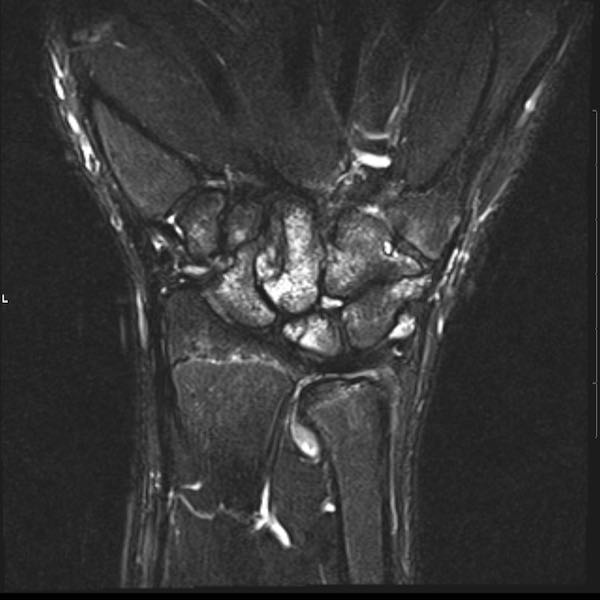

Tiếp tục xem hình ảnh MRI của bệnh nhân này.

Hình ảnh MRI:

Tràn dịch lan tỏa tất cả các khớp cổ tay.

Phù tủy xương lan tỏa tất cả các xương cổ tay.

Bào mòn xương, ví dụ tại xương thuyền, xương đầu và xương móc.

Phá hủy khe khớp và sụn khớp, rõ nhất tại khớp STT và CMC4/5.